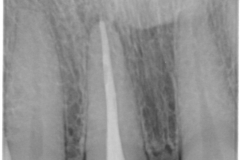

Il nostro Studio ha deciso di dotarsi di un sistema di radiografia digitale endorale con pellicole ai fosfori.

Una Scelta sofferta per la qualità forse ancora superiore dei formati in pellicola tradizionale, ma motivata dalle straordinarie prestazioni dello scanner di ultima generazione in dotazione all’apparecchio: legge e scarica sino ad 8 immagini per volta, le cancella e rende nuovamente e immediatamente riutilizzabili le pellicole ai fosfori.

• immagini ad alta risoluzione, comunque adempienti ad ogni requisito diagnostico;